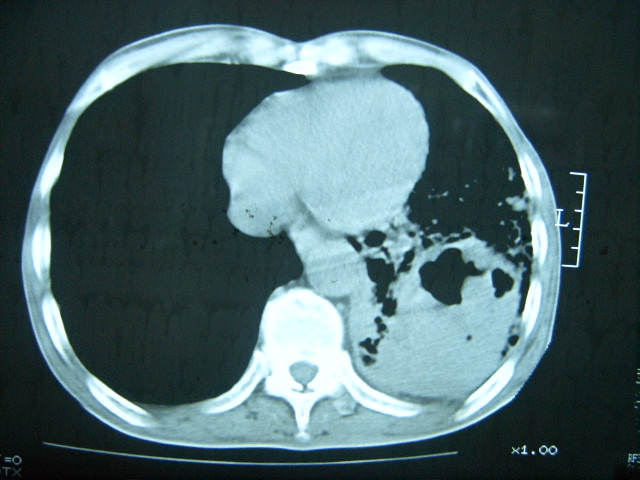

男74岁,咳嗽,寒战,低烧。有糖尿病史。

考虑:1、左下肺脓肿;

2、双肺结核。

考虑:糖尿病合并:1、左下肺炎继发肺脓肿;

两肺结核,左下肺大片实变,内见空洞性病变,壁不规则,结合糖尿病史,考虑:结核性?霉菌性?建议结合实验室检查或治疗后复查。